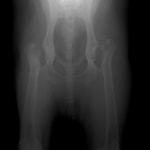

重度股関節形成不全の症例

ボール遊びの後の後肢の跛行を主訴に来院されました。院内ではモンローウォーク(腰を振って歩く歩様)が認められました。レントゲン検査において、左右股関節の形成不全および比較的重度の関節炎所見を認めました。左右ともに長期に及ぶ骨関節炎の進行により、寛骨臼に重度の骨変形・骨硬化が認められました。このような症例においては、THRのカップの定着が悪くTHRの手術の成功率が下がるため、機能回復の面では劣りますが、症状がより重く、筋肉の萎縮の認められた右後肢の大腿骨頭・骨頚切除術を実施しました。関節面に関節軟骨の欠損、骨増殖体を認めました。今後は、リハビリテーションを行い、患肢の機能回復に努め、反対側の大腿骨頭・骨頚切除術を検討していく予定です。

術前レントゲン